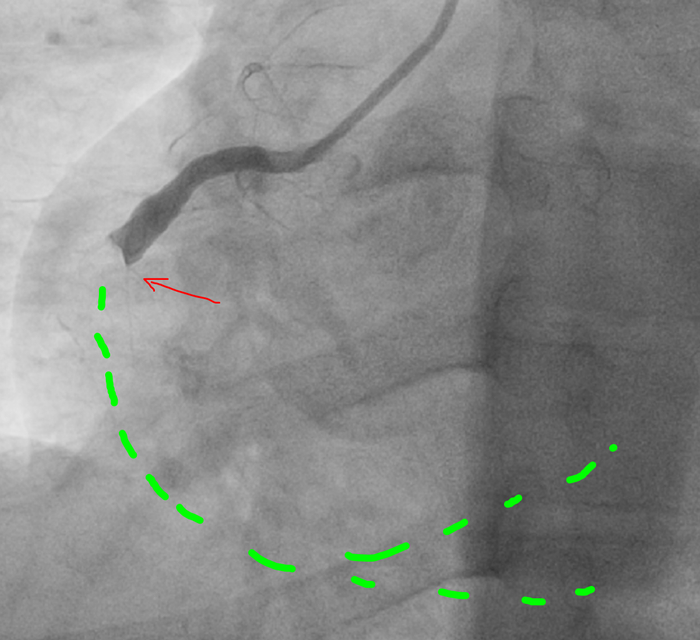

Ко второму курсу училища( училища, а не универа) я уже читал ЭКГ. Все основные случаи инфарктов, аритмий и блокад. Изучал все пленки ЭКГ.